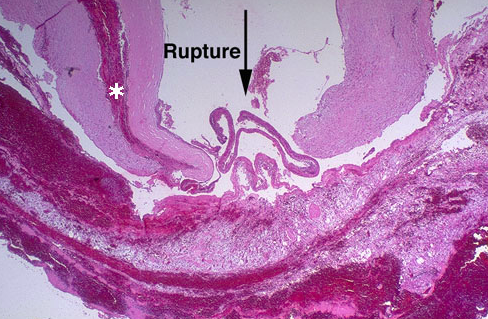

- Microscopically, the tear (arrow) in this aorta extends through the media, but blood also dissects along the media (asterisk)

16